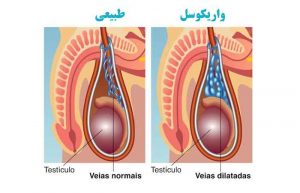

انواع بیماری واریکوسل ؛ از علت و علائم تا تشخیص و راه های درمان

چه رابطه ای بین واریکوسل و ناباروری وجود دارد؟

همه آنچه باید از واریکوسل خفیف بدانید